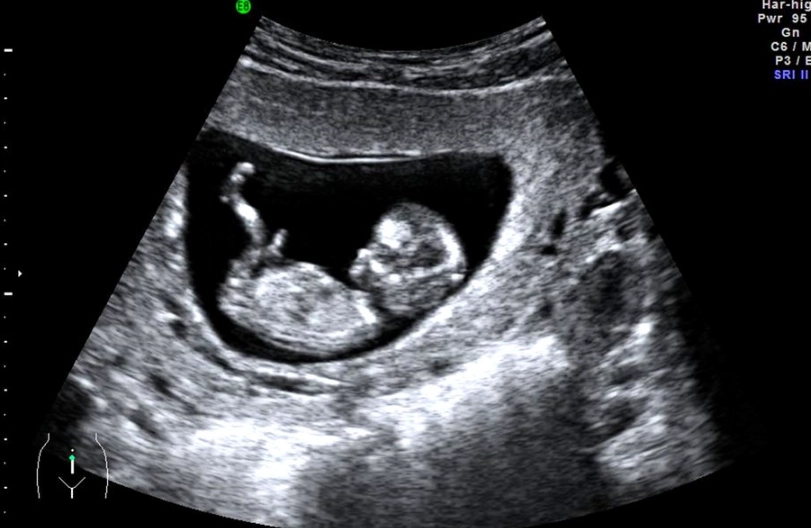

The Nuchal Translucency (NT) Scan

This is a specialized ultrasound usually done between 11 and 14 weeks. It measures the clear space in the tissue at the back of the baby's neck. An increased measurement can be a soft marker for certain chromosomal conditions, like Down syndrome. It's often combined with a blood test (the first trimester screen) to give a risk assessment, not a diagnosis.

I was nervous before mine. Seeing the baby move on the screen was incredible, but waiting for the results was agonizing. Remember, this is a screening test, not definitive. It just helps identify if further diagnostic testing (like CVS or amniocentesis) might be recommended.

Blood Work and Routine Checks

Your provider will likely check your weight, blood pressure, and listen to the baby's heartbeat with a Doppler (which can sometimes be heard at 12 weeks, but don't panic if they can't find it yet—the baby is still small and hiding!). Blood tests might check your blood type, Rh factor, iron levels, immunity to certain diseases, and screen for infections.